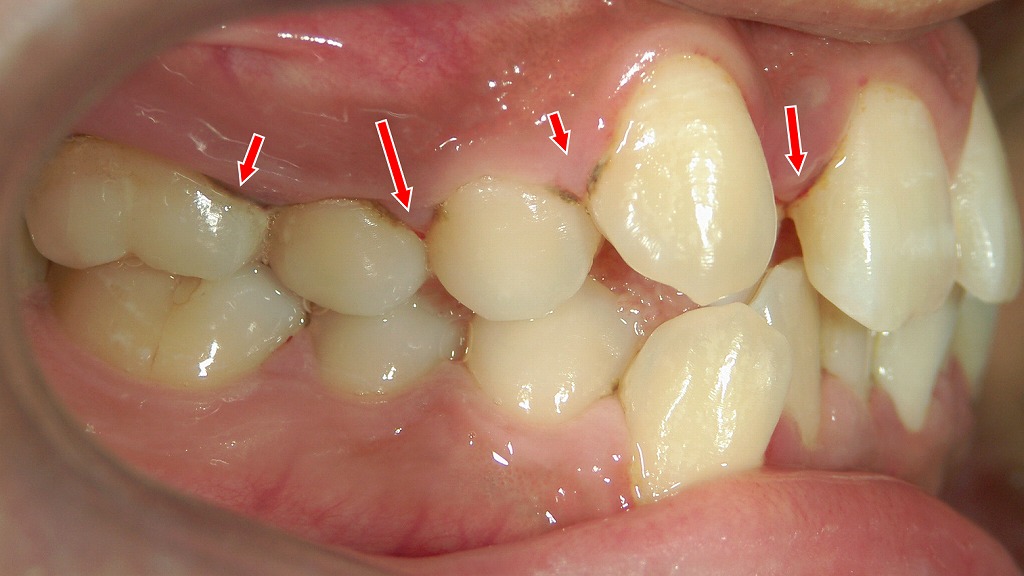

乱杭歯・段差に強い!ワンタフトブラシで守る歯ぐき健康

凸凹した歯並びの人は、普通のブラシだけで磨けたと思っても実際は汚れが残りやすく、虫歯・歯周病の発症率が高いことが知られています。

ワンタフトブラシを併用することで、磨き残し率を大幅に減らせます。

矯正治療中の歯垢染め出し液でチェック

この画像は、矯正治療中の歯にプラーク(歯垢)染め出し液を使用した状態を示しています。

🦷 全体の説明

歯の表面に紫〜ピンク色に染まっている部分がありますが、これはプラーク(歯垢)染色剤によって可視化された汚れです。矯正装置(ブラケットやワイヤー)がついていると、歯ブラシが届きにくくなり、ブラケットの周囲やワイヤーの下にプラークが残りやすくなります。

🔍 各部位のポイント

① ブラケット周辺のプラーク

- 金属のブラケットのまわり、特に**歯とブラケットの境目や歯頸部(歯ぐきに近い部分)**が濃く染まっています。

- これは歯ブラシの毛先が届きにくいため、プラークが残存している証拠です。

- 放置すると、ホワイトスポット(初期虫歯)や歯肉炎の原因になります。

② 歯肉の腫れと発赤

- 歯ぐきが赤く、やや腫れて見える部分があります。

- プラークの刺激で歯肉炎を起こしている可能性があり、出血しやすくなっています。

③ 染め出しの色の意味

- 濃い紫色:古いプラーク(数日以上残っているもの)

- 明るいピンク色:新しいプラーク(直近で付着したもの)

→ ブラッシングが不十分な部位を視覚的に確認するために使用します。

🪥 清掃方法のポイント

💡 通常の歯ブラシ

- ブラケットの上・下・正面を分けて磨く意識が大切です。

- ワイヤー下の清掃も角度を変えて行います。

💡 ワンタフトブラシの使用

- 写真のようにブラケット周囲に汚れが残りやすい場合、

ワンタフトブラシ(毛束が1本の小さいブラシ)が非常に効果的です。 - ブラケットの上下や歯と歯の間、ワイヤー下を小刻みに動かして磨くと、プラークを除去しやすくなります。

⚠️ 放置すると…

- プラーク内の細菌が酸を出し、**脱灰(初期虫歯)**が進行。

- 白く濁る「ホワイトスポット」や、装置除去後の虫歯・歯肉退縮につながります。